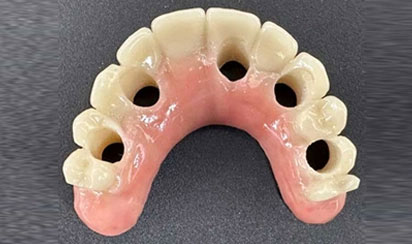

For your final teeth, you, the dentist, and our in-house lab technician will work together to design your perfect smile. While other offices still use acrylic denture teeth over titanium bars, we use zirconia for the best in appearance, durability, and resistance to staining. Upgrading to these materials usually costs significantly more at other offices. At Sumner Dental Group, they’re our standard.

Custom-Made (OUR)

Match to Existing Natural Gum Tissue

Minimal Invasive Surgery

Retrofitting (Others)

Counter-Top Teeth

Bulky Teeth